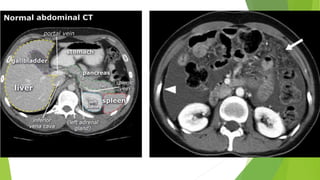

IMAGING

 XRAY

 CT

 ULTRASOUND